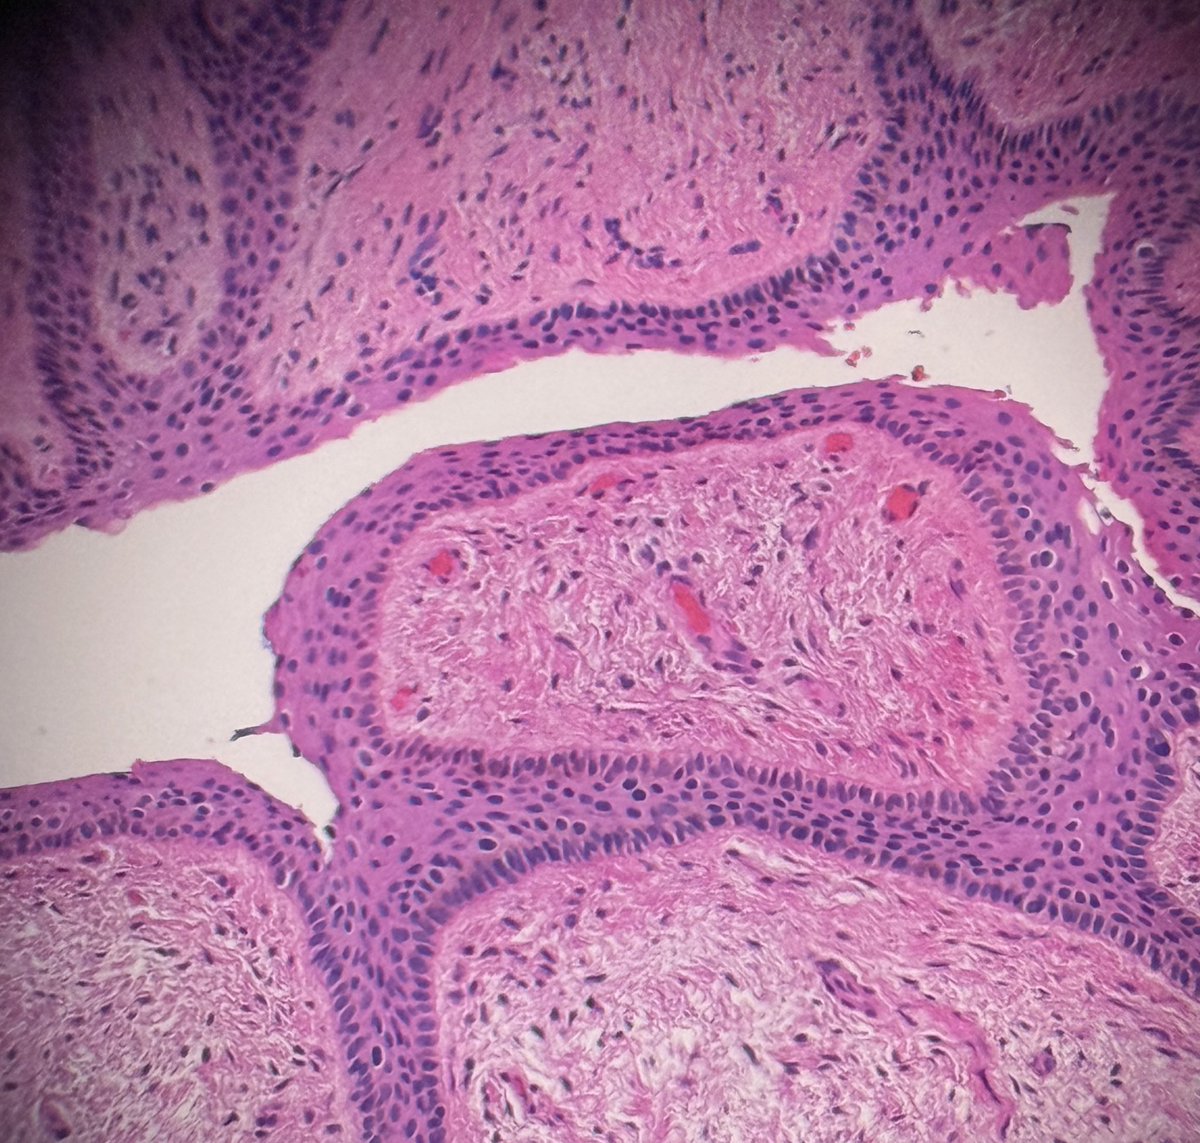

@HENRYY_MD has inspired me to post 66 year old female nail matrix biopsy. @HoustonArsenal @DrGeeONE @PIorfino @Dr_Jukic @kis_lorand #dermpath #nail #dermatology ๏ฟผ